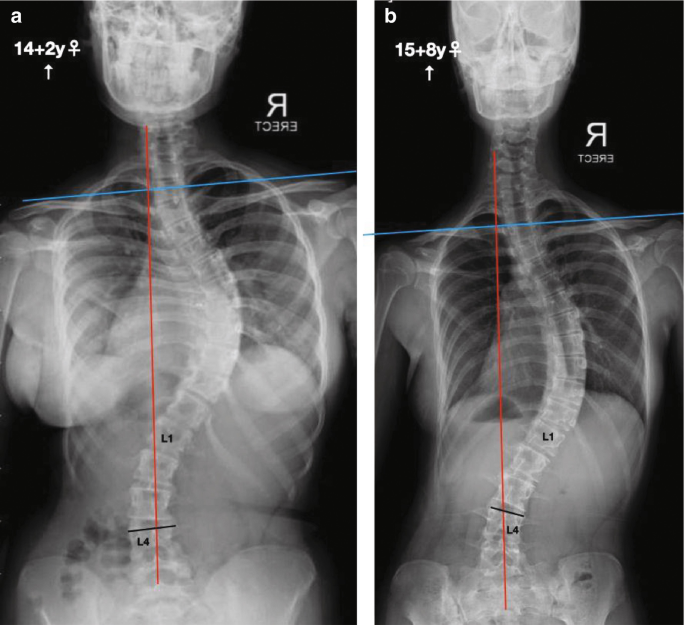

أجريت دراسة لمعرفة ما إذا كان شكل الانحناء وفقًا لنظام mLenke المعدل (mLenke) يؤثر على نتائج العلاج باحزام اعوجاج العمود الفقريي، خاصةً الحزام الخلفي TLSO. تم متابعة المرضى منذ بداية ارتداء الحزام وحتى نهاية العلاج أو اللجوء إلى الجراحة، مع مراقبة التزامهم بعدد ساعات ارتداء الحزام يوميًا.

الدراسة شملت 168 مراهقًا، تتراوح درجات انحناء العمود الفقري لديهم بين 25° و45°، وكانوا جميعًا في مراحل نمو مبكرة (Risser 0 إلى 2). تم قياس التزام المرضى بالحزام باستخدام جهاز حرارة رقمي، كما تم تقييم الانحناءات بالأشعة عند بداية العلاج ونهايته.

تم تصنيف الانحناءات وفقًا لنظام mLenke المعدل كالتالي:

mLenke-I: الانحناء الرئيسي في منتصف الصدر.

mLenke-II: انحناء مزدوج في منتصف الصدر.

mLenke-III: انحناء كبير في منتصف الصدر مع انحناء ثانوي في أسفل الظهر.

mLenke-V: الانحناء الرئيسي في أسفل الظهر.

mLenke-VI: انحناء مزدوج في أسفل الظهر.